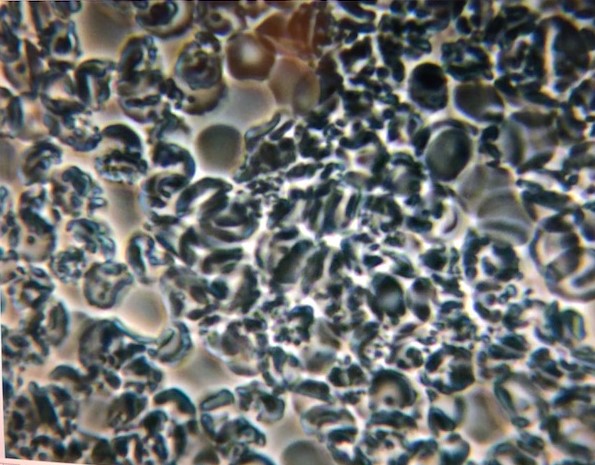

The ten days of cleansing, juices, exercising, getting to bed early and no television, did wonders for my body and mental well being. I had dreaded the idea of not eating solid food for ten days, but during the period, I never felt hungry. In fact, I felt so energized , it was surprising. Doctor Rudy explained that the juices are packed with nutrients and are more bio-available than solid food. To top it off, I was blown away by the live blood analysis at the end of the program! It seemed like the blood of a different person, indeed I felt like a different person!

Blood sample AFTER cleanse

Blood sample before cleanse